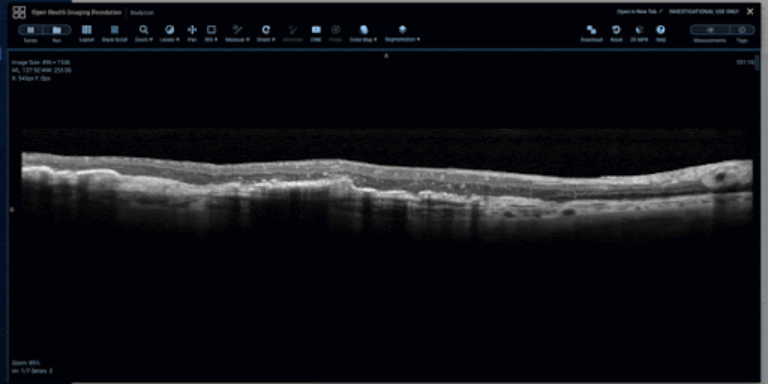

As shown below, the viewer supports an open freehand tool for retinal layer tracing, a closed freehand ROI tool for capturing distinct findings, such as intraretinal fluid pockets, and a sculpt tool for precise editing of freehand ROIs.

Closed Freehand ROI tool for capturing distinct findings.